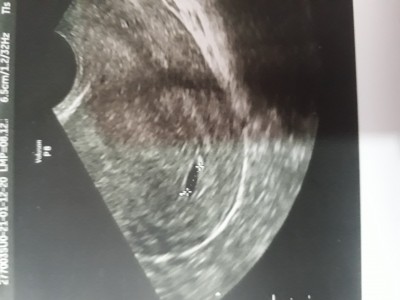

image

şöyle bir kese göründü

Canim dış gebelikte rahme yerleşen bu kese olmaz çünkü yumurtalıklarda döllenme olur ve orda kalır ki adı dış gebelik hiç canını sıkma benim geçen sene dış gebelik yaşadım ve değerler hiç de senin söylediğin kadar yüksek değildi içini ferah tut

Keseyi bebeği gördüm . 3 ay önce kürtaj oldum kalp atışı durmuştu